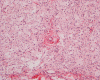

Clinical information The patient presented with a 3.0 x 3.0 x 1.5 cm subcutaneous mass in the lateral thigh. The mass was excised under the clinical impression of a sebaceous cyst. Macroscopically, the excised specimen is not covered with skin. The following photos are representative photomicrographs of the mass.

Histologically, the mass has a pushing margin attached with a scant number of skin appendage at one surface of the mass which confirms its superficial location. On low-magnification, the mass has a storiform arrangement of tumor cells that are intermingled with a significant amount of rather broad collagen fibers (Panel A and B). The tumor cells vary from bland, spindle cells with minimal xanthomatous changes (Panel C and D) to polygonal, foamy xanthomatous cells (Panel E and F). The storiform arrangement is more commonly encountered in the periphery and the foamy xanthomatous component is more prominent at the core of this mass. The dense collagen fibers with morphological features comaparable to that of keloid are present and are best demonstrated by Masson's trichrome stain (Panel G). Hemosiderin laden cells can be seen. These cells are far more prominent under the microscope then on the screen. On a histologic stain to demonstrate iron, the depositions are fine and widely distributed. The amount exceeds the expectation based on observation by hematoxylin-eosin stain  (Panel H). Giant cells were not readily seen.